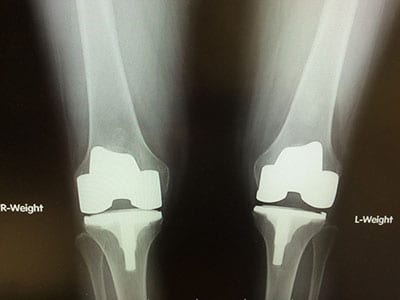

Knee joints are likewise often made from titanium and ceramics. The use of ceramics may be required in metal sensitive patients, although ceramic joints are much more common outside of the United States. When considering which joint replacement is right for a patient, the surgeon takes many variables into account, such as weight, bone dimensions, the health and strength of ligaments, probable activity levels, gender, and patient age. Design features are also a consideration, as younger patients may require a more conservative approach to maximize the preservation of bone, while an older patient may need a replacement that is much less robust.